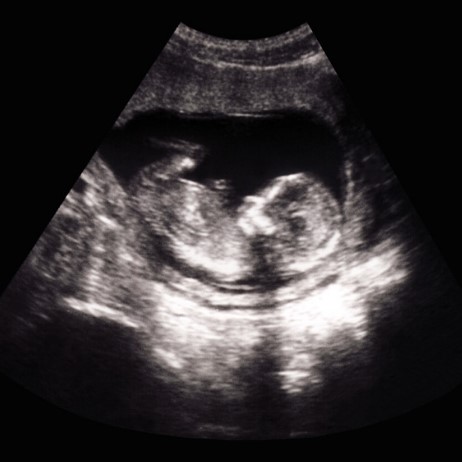

Al principio del embarazo, ciertos hallazgos ecográficos, como la presencia de un saco vitelino y la relación entre la coronilla y la rabadilla, se utilizan para ayudar a determinar la salud de un embarazo, la edad gestacional y la posibilidad de pérdida del embarazo. Después del primer trimestre, el embrión se ha convertido en un feto y se utilizan nuevos marcadores para acotar la edad gestacional y evaluar la salud del bebé.

Uno de los marcadores utilizados para evaluar el crecimiento y la salud del feto es la longitud del fémur del bebé, el hueso largo del muslo. La longitud del fémur, que se mide desde el extremo romo del hueso hasta el eje, se suele medir en milímetros.

Un hallazgo de longitud de fémur corta en la ecografía puede indicar la necesidad de realizar más pruebas para descartar ciertas afecciones. Pero también es importante tener en cuenta las limitaciones inherentes al uso de la longitud del fémur como marcador de malos resultados del embarazo.

Cuando la longitud del fémur está por debajo del quinto percentil, se puede advertir a los padres sobre una serie de posibles resultados atípicos del embarazo. Una longitud de fémur corta identificada en la ecografía en el segundo o tercer trimestre suscita preocupación por las afecciones que se detallan a continuación.

Sin embargo, esta medición tiene muchas limitaciones, desde el error humano hasta el equipo de ultrasonido anticuado y la variación normal. La longitud del fémur es sólo una variable entre las muchas que deben utilizarse para determinar la salud del bebé.